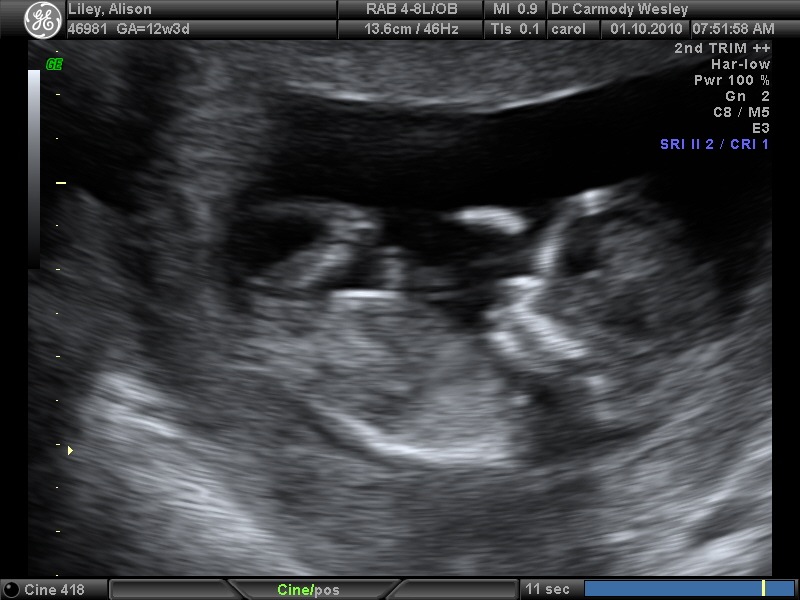

It's been hard to keep this all under wraps for the past 12 weeks while we waited for the socially appropriate time to spread the word. Friday was the first of many tests that this child will have to endure in it's life and I'm pleased to say that it's already excelling all standard benchmarks. Admittedly my assessment could be considered marginally biased.

That's a beautifully formed left hand I think. Absolutely perfect for playing the guitar and video games as you would expect. One thing that doesn't come across in the pictures is how much the baby moves during the ultrasound. We were absolutely transfixed on the screen, watching in awe as the baby (a mere 5.5cm from crown to rump at this point) floated around and danced on the screen. I'd buy one of those machines to take home if I could.

There were also 3D pictures taken but they didn't come out as well. I'm going to be taking a lot of photos over the next few years so this kid better not be camera shy. Fascinating that it sleeps the same way I do with my arm over and face against the wall. Well... I found it fascinating anyway.